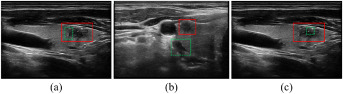

图1. 超声视频分割的挑战:(a) 模糊边界,(b) 混淆位置,(c) 散斑噪声,红色轮廓指甲状腺结节,绿色轮廓指混淆区域。